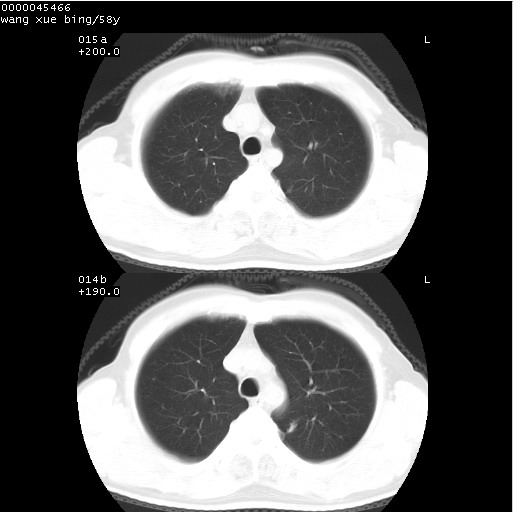

患者 男,58岁。咳嗽、咯血3月余。

胸部ct轴位平扫(层厚10mm,螺距1.5,重建间隔10mm),图像如下:

右肺下叶团块及不规则空洞,内壁不规则,外缘见粗长毛刺,临近胸膜明显增厚并与病灶关系密切。支持考虑:右肺肺脓肿!建议穿刺病理检查待除外周围型肺癌!

右肺下叶见不规则厚壁空洞,内壁不规则,外缘见粗长毛刺,临近胸膜明显增厚并与病灶关系密切。支持考虑:周围型肺癌!

右肺下叶周围型肺癌伴空洞形成!征象比较明显!分叶、毛刺、胸膜凹陷征、厚壁空洞,壁结节!

空洞壁厚,不规则,其内可见壁结节,周围可见毛刺及阻塞性炎变,多考虑癌性病变.

空洞内壁不规整,有壁结节,周围有毛刺,支持癌性空洞。